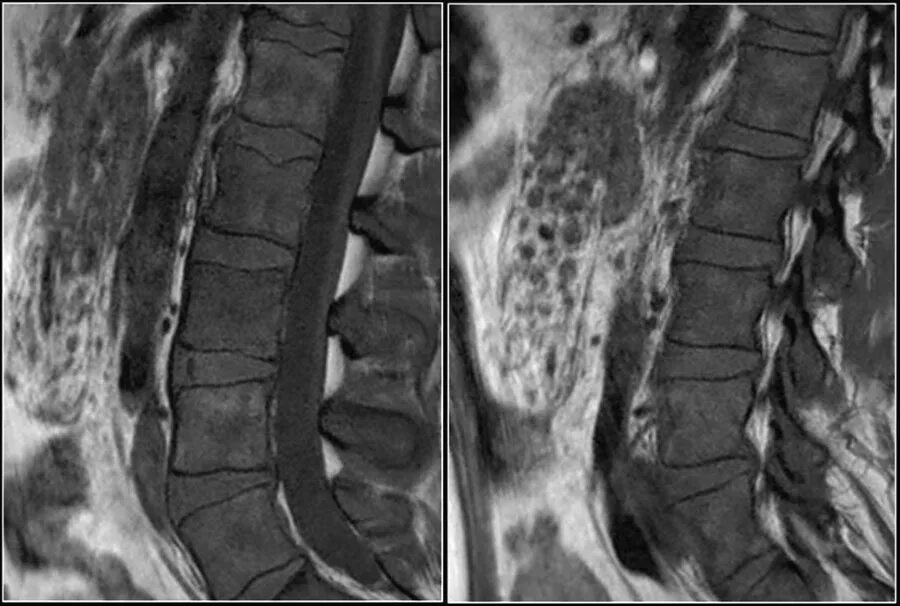

Грыжа диска мрт